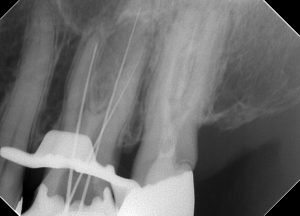

湾曲部より先で破折しているファイルがあります。

なんとか取れました(^^♪

これ、ニッケルチタンファイルでした( 一一)

NTはなかなか取れないです。

ステンレスファイルはテーパーが02なので上のほうが遊びがあるんですが、NTは04や06テーパーのファイルが多いため、なかなか遊びがないため、超音波で振動させるときになかなか共振しないんですね( ;∀;)